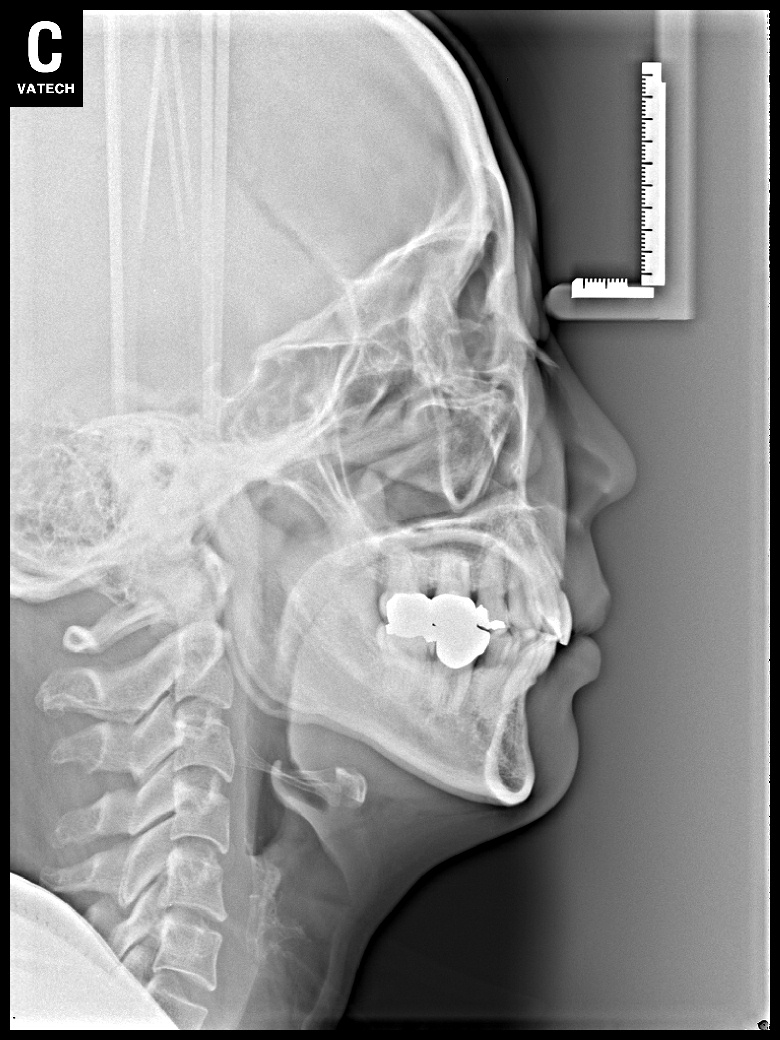

치료 후 사진입니다.